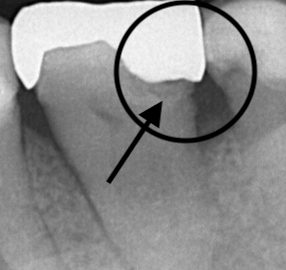

- 2020/10/08 金属の下にできる虫歯

こんにちは、静岡市駿河区にある歯科医院、小嶋デンタルクリニックです。 歯医者さんに検診で行った際に、銀歯の下に虫歯ができている、銀歯と歯に段差ができていると指摘を受けたことがある方いますよね。 … 続きを読む 金属の下にできる虫歯

→ 続きを見る